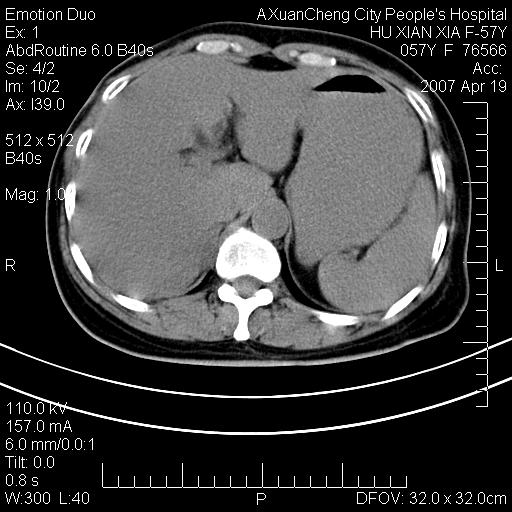

标题: CT7778:[原创]F,57Y腹痛待查,胸片提示肺部占位,应当很典型 [打印本页]

标题: CT7778:[原创]F,57Y腹痛待查,胸片提示肺部占位,应当很典型

胸片提示肺部占位

考虑:1、双侧肾上腺占位.2、肝左叶内侧段不规则低密度灶,建议强化扫描.

忽略了,只以为急腹症,应该支持肺癌肾上腺转移,肺癌患者20-30%发生肾上腺转移

双侧肾上腺增大,有分叶,密度均匀,考虑转移建议查原发灶

1.双侧肾上腺占位,转移首先考虑。

2.肝硬化,门静脉高压;肝左叶内侧段病灶建议增强。

支持肺癌肾上腺转移,肺癌患者20-30%发生肾上腺转移

双侧肾上腺结节样肿块,结合肺部肿块,考虑肺癌肾上腺转移。

双侧肾上腺及腹膜后淋巴结增大,结合胸片提示肺部占位,考虑肺癌双侧肾上腺及腹膜后淋巴结转移.